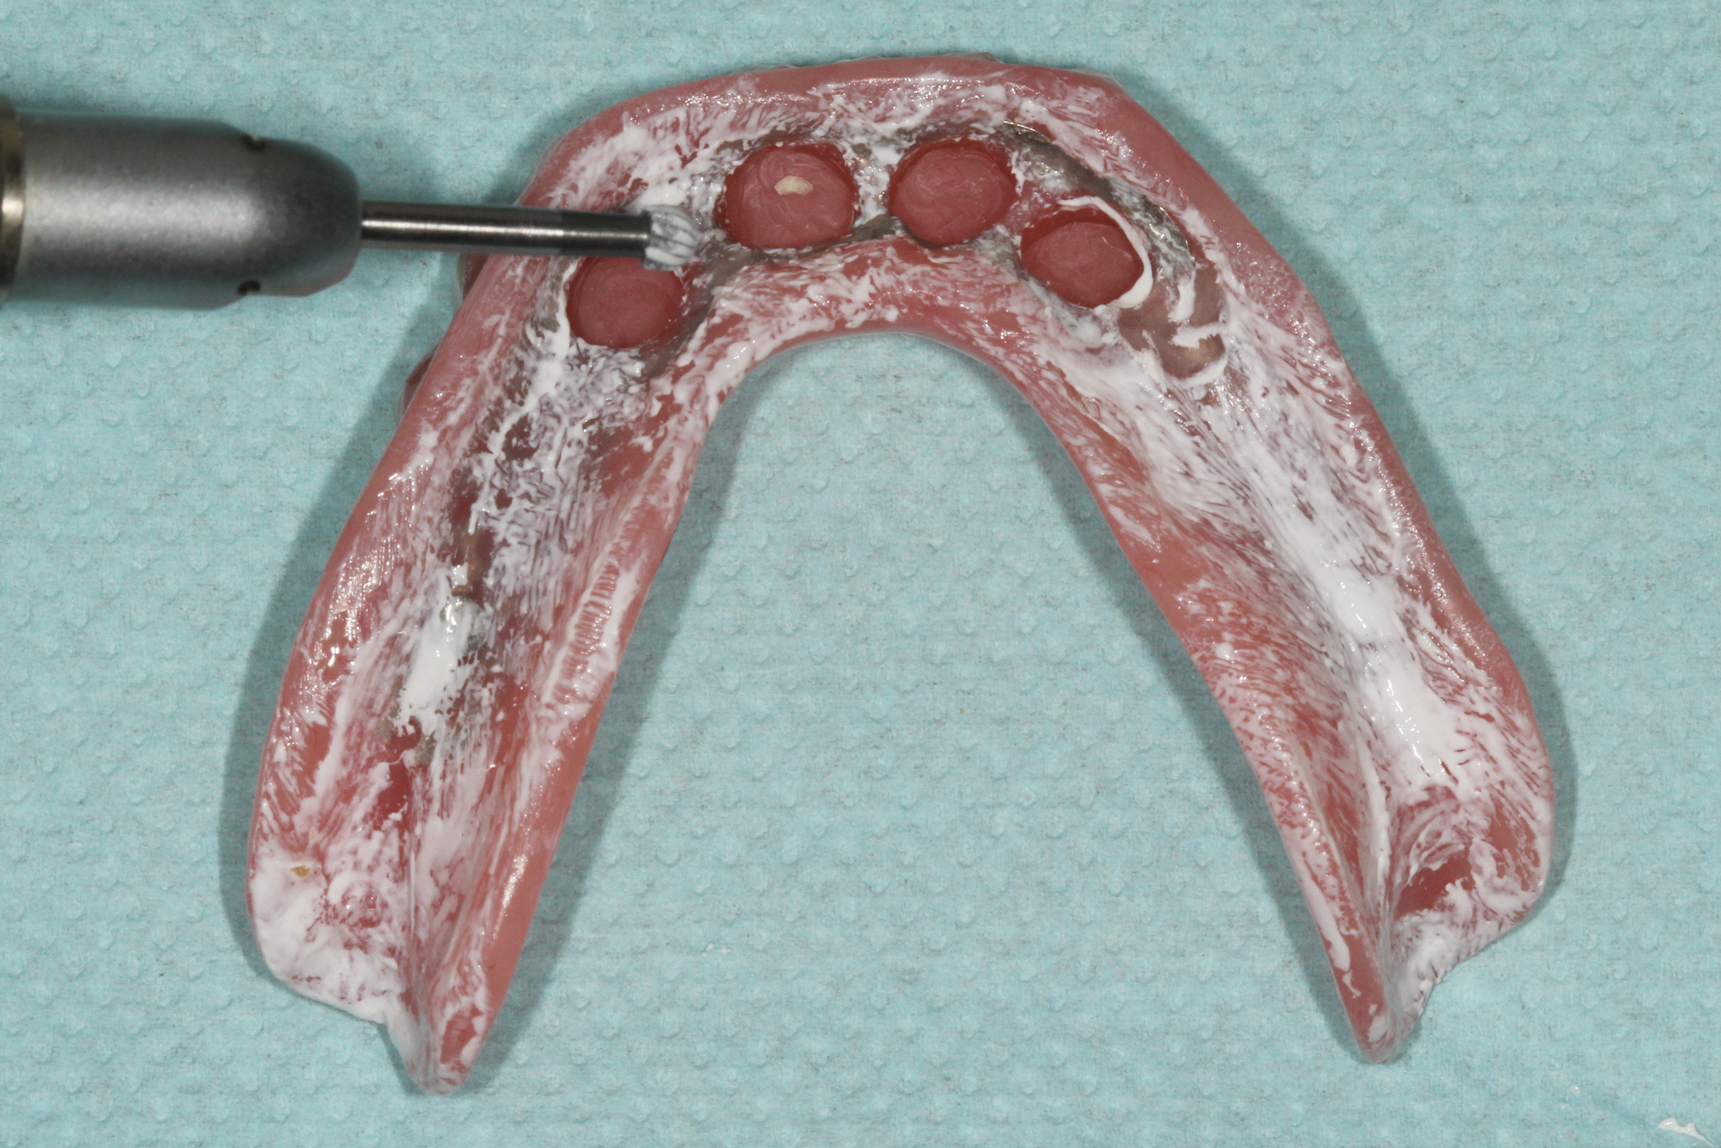

Prosthetic adjustments to the areas of excessive pressure were made using acrylic burs to relieve the areas of paste displacement. First, any pressure areas caused by occlusal forces were adjusted by relieving the areas where heavy pressure was noted with a medium- to large-sized round bur using moderate speed and light force (Figure 8). The anteroposterior pressure areas were adjusted next, and the oblique pressure areas were adjusted last. Both of these pressure areas, which are typically visualized with longer, narrower areas of paste displacement, were adjusted with a tapering acrylic bur using low speed and moderate force. A highspeed handpiece with a large football-shaped carbide bur can assist in adjusting any areas where a metal framework is in excessive contact with the soft tissues.

(3.) Intaglio view of the laboratory processed complete denture with a metal substructure and ideal recesses prepared.

Figure 3

(8.) Acrylic burs used to adjust any areas of excessive pressure.

Figure 8